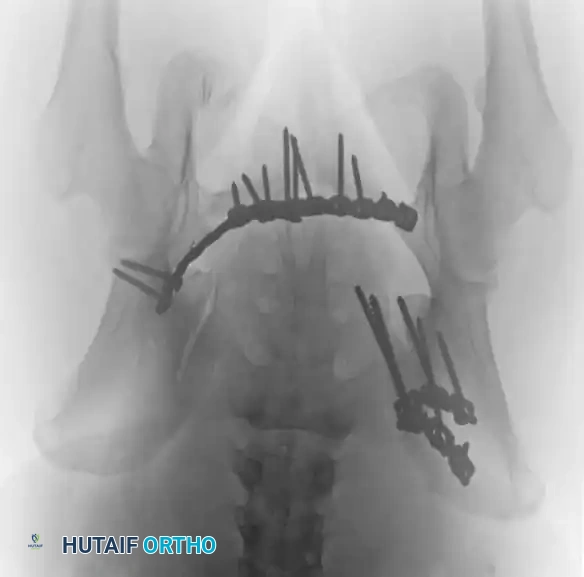

4. Posterior Tension Band Plating

For comminuted sacral fractures or when percutaneous corridors are unsafe, open reduction and posterior tension band plating (or lumbopelvic fixation) may be required. This involves placing plates across the posterior ilium to the sacrum, effectively recreating the posterior ligamentous tension band.

Image